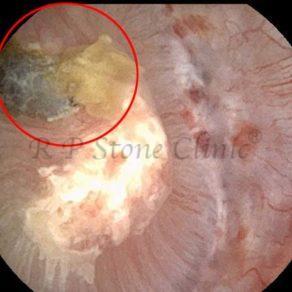

Kidney stone is a solid mass of CRYSTALS. It is the process of crystallization which initiates the formation of kidney stones. This happens in nephrons or units of kidney. Once a small crystal is formed, it can both grow & unite with other crystals leading to the formation of small concretion which eventually forms a stone. Once these large crystals detach from the collecting ducts, the process of stone formation starts in the renal collecting system. A recurrent kidney stone former is advised to know a little bit about something known as Randall’s plaque. Alexander Randall discovered plaques on the renal papillae eight decades back based on examination of 1154 pairs of autopsied Kidneys. He described these renal papillary lesions as cream colored or milk patch areas composed of calcium phosphate & calcium carbonate. These plaques could act as NIDUS for formation of KIDNEY STONE. Calcium Oxalate stone can form on this nidus & then detaches from this plaque to become a free floating stone in the collecting system of kidney

These images are taken as snap shots from the video recording of RIRS Surgery done at our hospital. These are Randall’s Plaques seen with Digital FLEX XC & Digital FLEX XC S. The cream or whitish patches are seen on the tips of RENAL PAPILLAE as seen in images below.

Randall’s Plaques may lead to the formation of Stones.